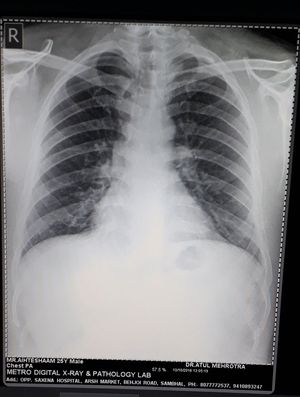

Diagnose the CXR

A pateint with the history of #smoking and # mild cough. #Age 25 years #young man